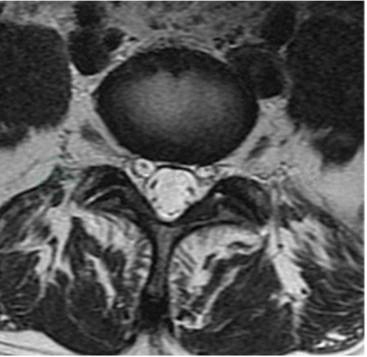

横轴位:椎体与椎间盘呈肾形,椎间盘在T1WI呈低信号,T2WI中央髓核为椭圆形高信号,周围纤维环为低信号。脊髓圆锥末端位于椎管中线稍靠后部,周围有许多神经根围绕,前部的腹侧神经根常呈V形、后部的背侧神经根多呈W形围绕圆锥和终丝。脊髓圆锥向下移行为纤维性终丝,止于盲囊。自圆锥平面向下走行的腰骶神经根称为马尾。圆锥和马尾在T 1WI为中等信号强度,类似于椎间盘信号,在T2WI信号强度低于椎间盘和脑脊液信号。马尾的形态在不同层面各不相同,在圆锥平面呈蜘蛛足样;在L2平面盲囊的下垂部为新月形软组织块影信号;在L3平面为新月形、球形或不规则形;在L4水平神经根均匀散布于脑脊液内;在L5水平稀少的神经根散布于盲囊内。在正中矢状位神经根显示为沿盲囊后部的线样中等信号影,旁正中矢状位显示神经根呈扇形从后向前下方延伸。

腰椎椎管横断面在上腰部常呈圆形或卵圆形,在下腰部多为三角形,其尖端指向后方,横径多大于前后径,腰段硬膜外间隙内含有较多的脂肪,大多位于硬膜囊前方和前外方,因此可较好地对比显示出椎间盘突出对硬膜囊的压迫。腰段蛛网膜下腔比颈、胸段宽大,尤其在L 2以下水平,MRI图像可清晰显示硬膜外脂肪和宽大的蛛网膜下腔。